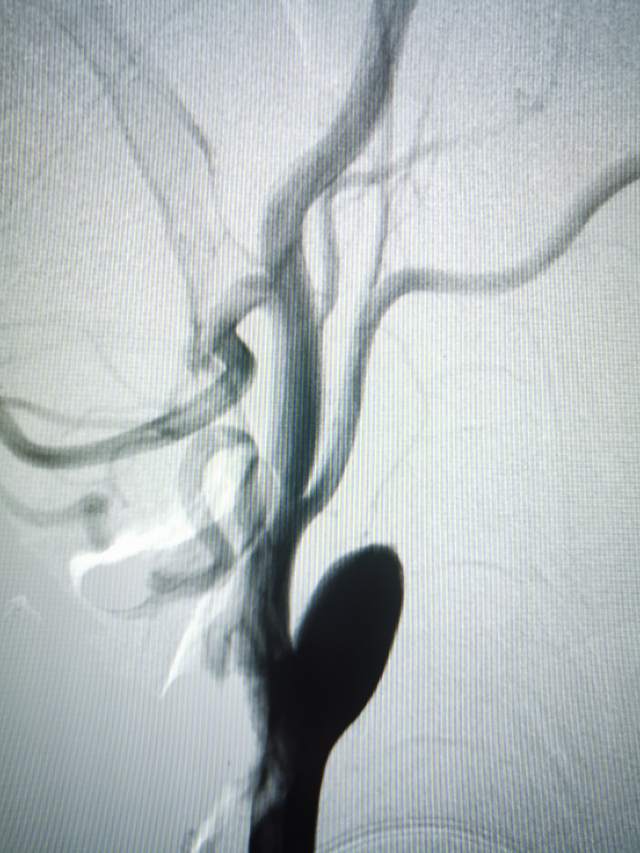

头颅MRI提示:左侧分水岭区点状脑梗塞,右侧半卵圆区脑梗塞。左侧散在的多发点状脑梗塞位于分水岭区,梗塞原因:1、低灌注;2、蹼导致的泥沙样栓子脱落。更严格来说,蹼导致的血流紊乱引发单位时间内通过同一个横截面的有效循环血流量的降低所致,泥沙样栓子可能参与其中。

因此,这个左侧脑梗塞与左侧颈动脉蹼(左侧颈内动脉的起始部感觉被人砍了一刀)相关,属于症状性蹼,长期口服抗血小板药物无效,进行外科干预是审慎的和妥当的。